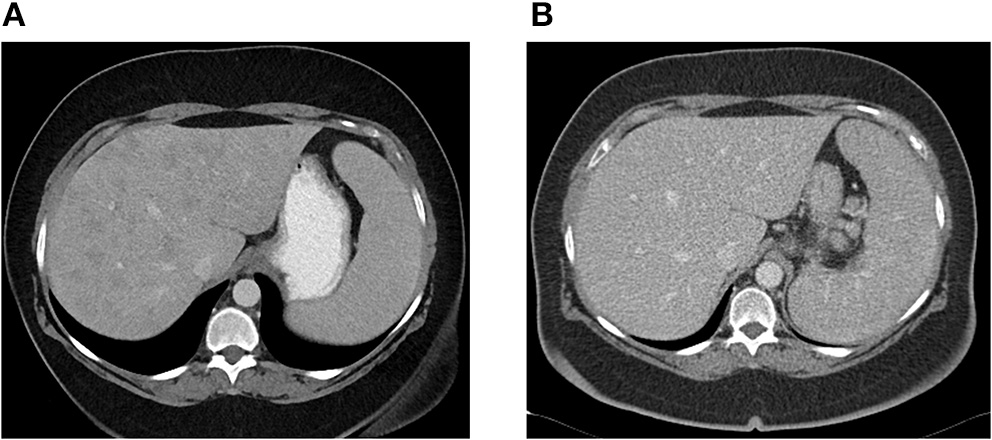

Patient CE was the most striking example: a 71-year-old female who presented 10 years prior with elevated ALP and liver biopsy showing portal granulomas, some bile duct loss and portal fibrosis. She was diagnosed with AMA-negative PBC, initially with complete response to ursodeoxycholic acid. Five years later, due to persistent elevation of ALP, additional work-up was performed with repeat liver biopsy, ACE level and CT scan (Figure 2). The biopsy showed multiple coalescing well-formed epithelioid granulomas in all zones. Marked lymphocytic infiltrates were present in portal tracts and in the lobules but florid duct lesions were not seen (Figure 3). The ACE level was elevated, 1.6–2 times the upper limit of normal, and the CT abdomen showed innumerable low-attenuation nodules of varying sizes scattered through the right and left lobes of the liver, worsening lymphadenopathy in the upper abdomen and mild splenomegaly (Figure 2). Those changes were definitely not present on prior imaging.

Figure 2

(A) Abdominal CT showing innumerable low attenuation nodules consistent with hepatic sarcoidosis. Patient was previously diagnosed with AMA-negative PBC, later re-evaluated and diagnosed as sarcoidosis. (B) Abdominal CT 6 months later, after patient was successfully treated with azathioprine with resolution of hepatic nodules.